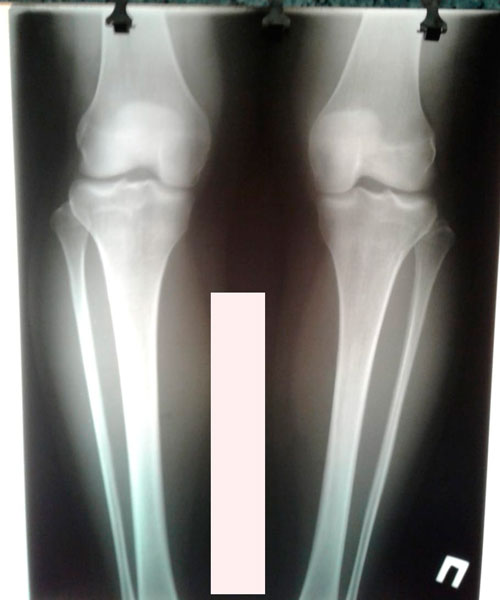

Исходник - 31 год.

Дата операции - 28.02.2019г.

Ротация с обеих сторон 30 градусов.

Дата снятия аппаратов - 30.05.2019г.

Срок сращени - 90 дней.